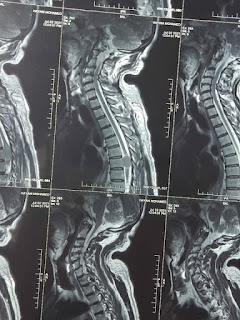

في عملية دقيقة ونوعية على المستوى الإقليمي، تمكن الدكتور جمال أوملال اختصاصي في جراحة الأعصاب، أمس الخميس 05 غشت2021 بالمركب الجراحي بالمركز الاستشفائي الإقليمي سيدي حساين بناصر بورزازات، رفقة الطاقة التمريضي المشرف على العملية من إزالة ورم على مستوى النخاع الشوكي لرجل يبلغ من العمر ستون عاما.

وقد تمت هذه العملية في ظروف حسنة وبدون أي مضاعفات، وبهذه المناسبة يتقدم مدير المركز الاستشفائي الإقليمي بورزازات بأسمى عبارات التهاني والتقدير للطاقمين الطبي والتمريضي اللذين أشرفا على إنجاح هذه العملية الدقيقة، متمنيا لهم المزيد من التألق والنجاح في مشوارهم المهني، كما يتوجه لعائلة المريض بدعواته الخاصة بالشفاء العاجل.